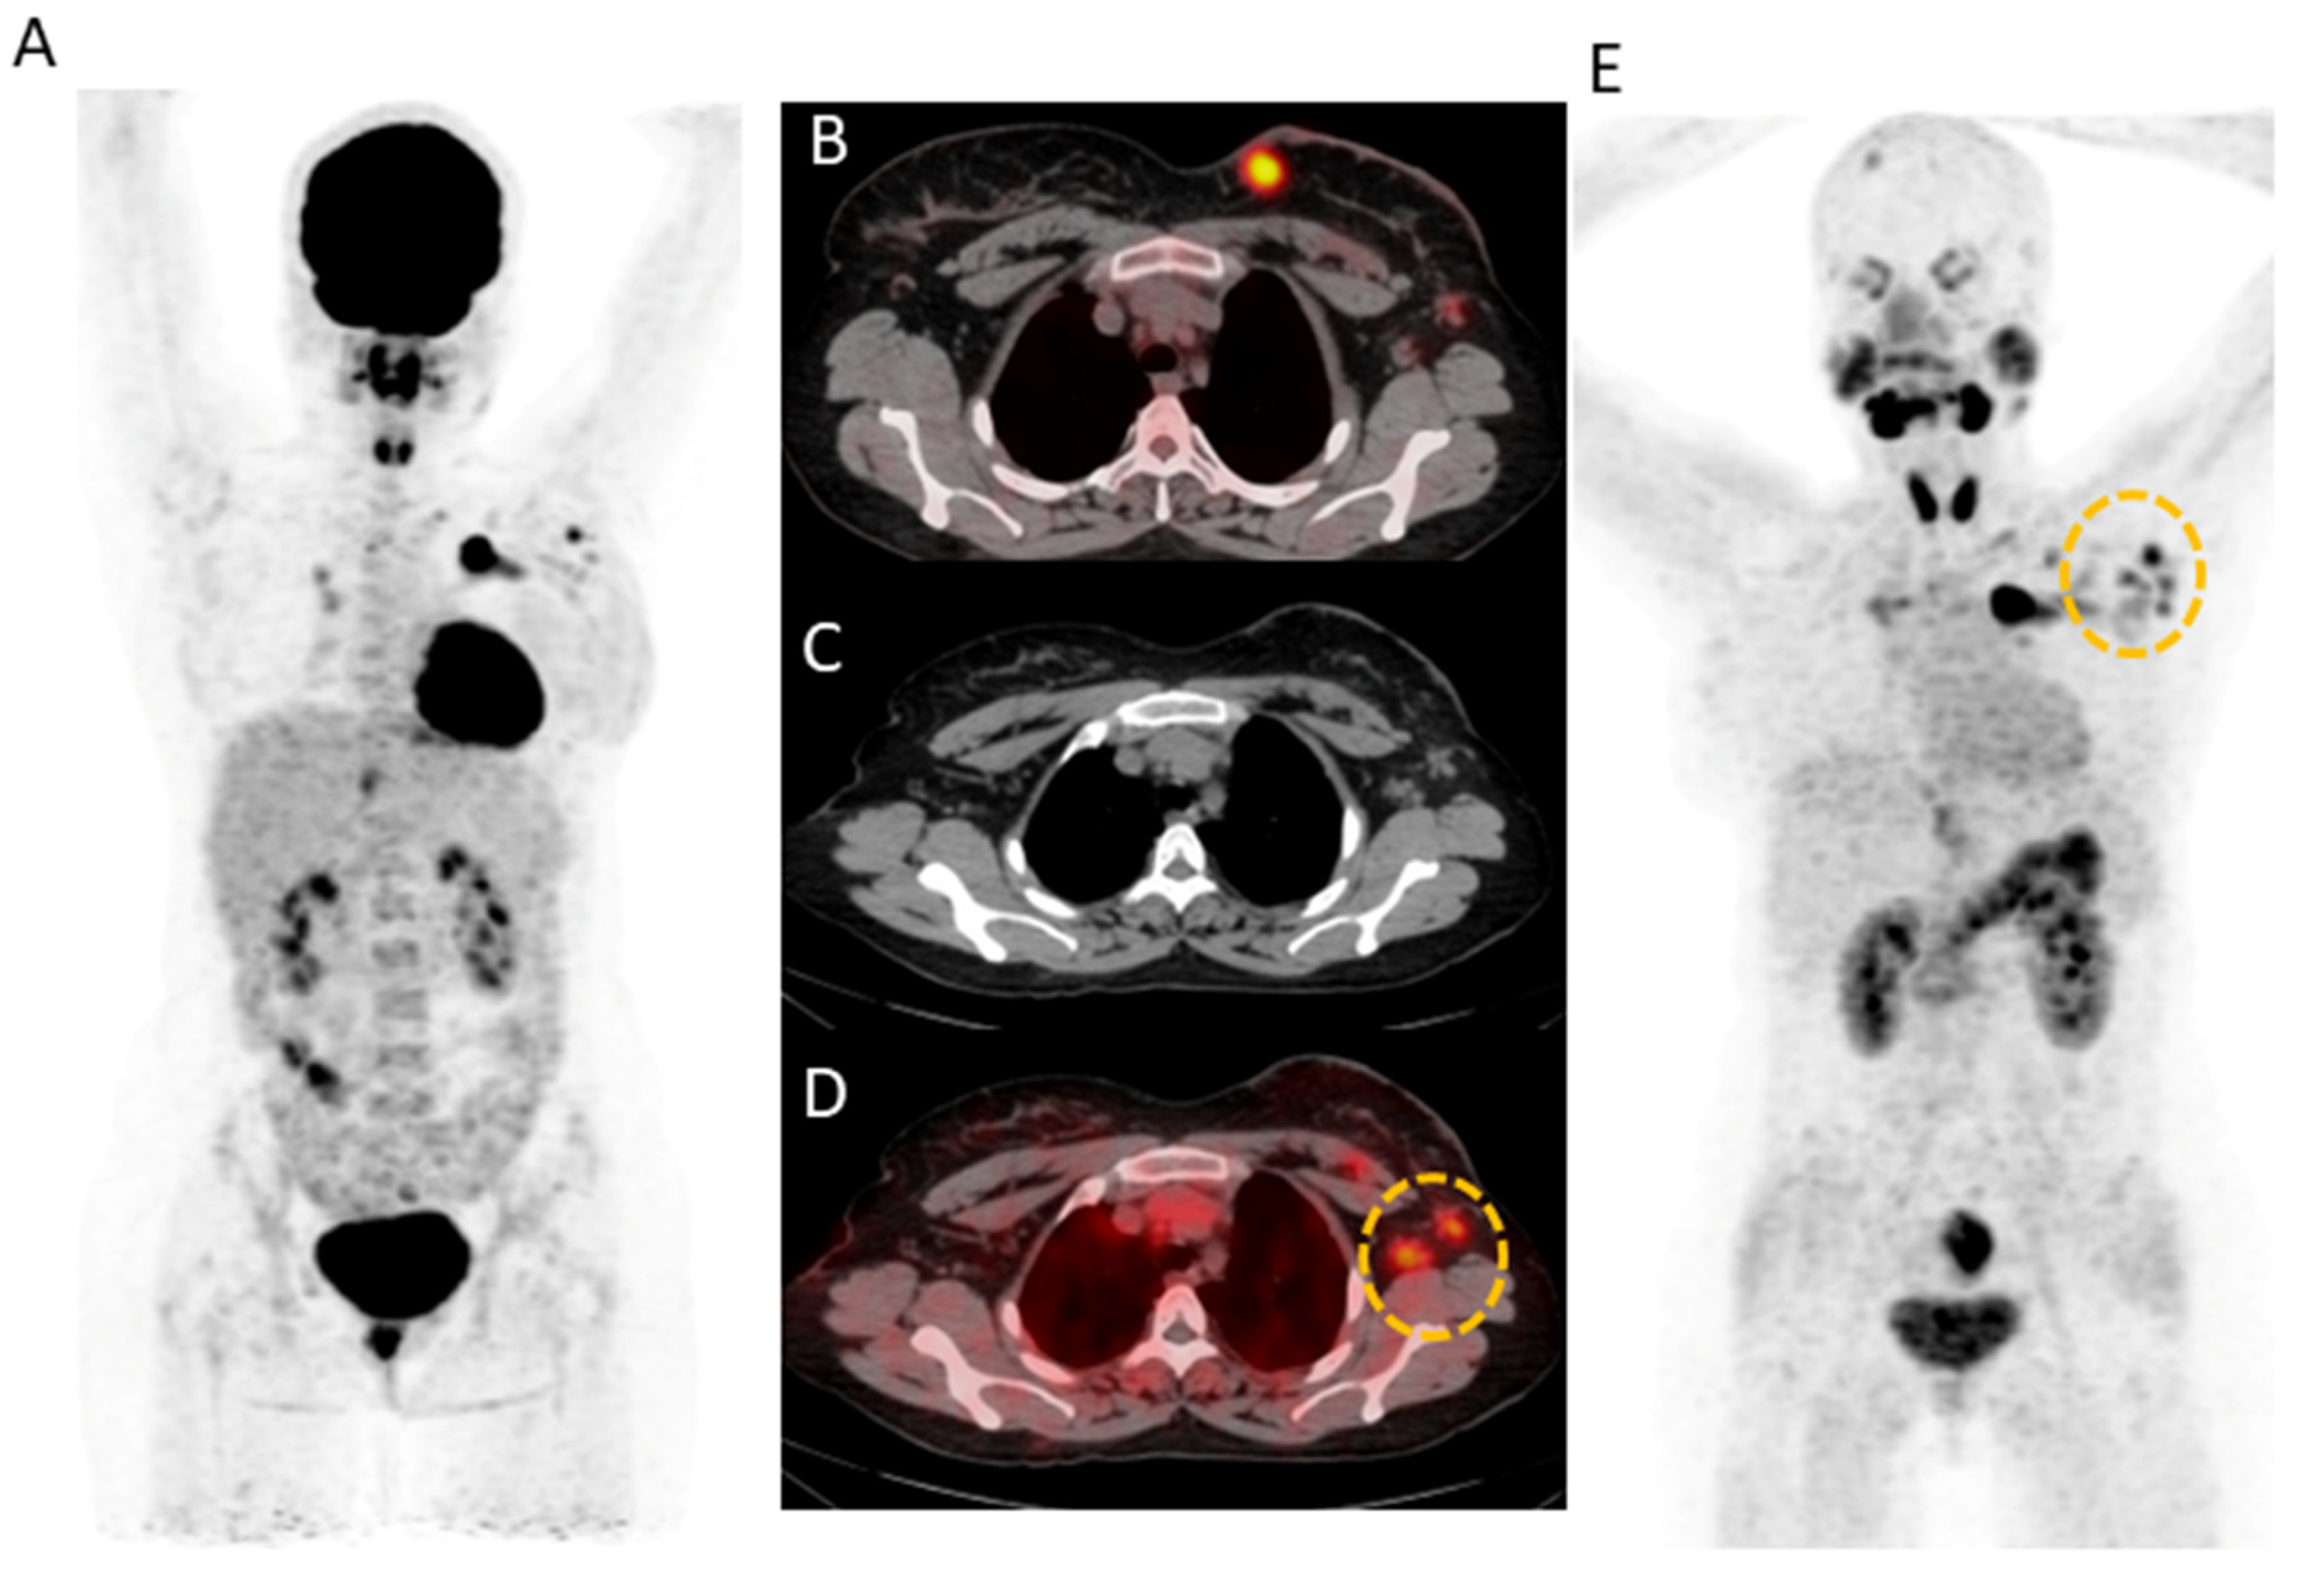

[68Ga]Ga-DOTA.SA.FAPi detected 221/248 lymph nodes (89.1%) compared to 208/248 (83.8%) lesions detected by [18F]F-FDG. A 31-year-old female underwent modified radical mastectomy (ER+/PR+/Her2-) followed by chemotherapy and was evaluated for response assessment. In this patient, [68Ga]Ga-DOTA.SA.FAPi showed increased radiotracer uptake noted in the left axillary level I and II lymph node corresponding to the CT compared but no avidity was observed on [18F]F-FDG (yellow circle) (FN). On the other hand, [18F]F-FDG showed diffuse non-specific radiotracer uptake in the entire axial skeleton, which is likely reactive (FP) (Figure 3).

Figure 3.

(A) 31-year-old female underwent modified radical mastectomy (ER+/PR+/Her2-) and 2 cycles of docetaxel chemotherapy. [18F]F-FDG (A,B) and [68Ga]Ga-DOTA.SA.FAPi (E) avid irregular mass (measuring 2.6 × 2.4 cm) noted in the breast upper inner quadrant. [68Ga]Ga-DOTA.SA.FAPi showed increased radiotracer uptake noted in the left axillary level I and II lymph node (D) corresponding to the CT (C) as compared to that of [18F]F-FDG (yellow circle). [18F]F-FDG shows diffuse non-specific radiotracer uptake in the entire axial skeleton, which is likely reactive (A).